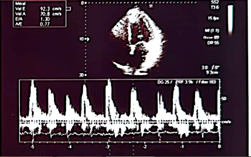

Control echocardiogram is performed

We can appreciate the amazing size left ventricle and normal global and segmental contractility with normal left ventricular ejection fraction (75%). Previous 10%. In addition, the patient was asymptomatic from the cardiological point of view. In such a way that all the medication that was started for the treatment of dilated cardiomyopathy was suspended, such as: Sacubitril/valsartan, furosemide, aldactone, ivrabadine, metoprolol, oral anticoagulants. The only treatment for her arterial hypertension was left with candesartan 16 mg per day and rosuvastatin 40 mg at night for mixed dyslipidemia. The following 6 patients 5 are male with ages: 28, 33, 35, 85 and one female: 95 years of age whose ejection fractions were similar 18, 17, 16 and 15% respectively and their evolution is similar to that of First case with an echocardiographic and clinical evolution to total normality. All patients currently lead a completely normal life.1-3